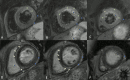

The Society for Cardiovascular Magnetic Resonance (SCMR) is an international society focused on the research, education, and clinical application of cardiovascular magnetic resonance (CMR). Case of the week is a case series hosted on the SCMR website ( https://www.scmr.org ) that demonstrates the utility and importance of CMR in the clinical diagnosis and management of cardiovascular disease. Each case consists of the clinical presentation and a discussion of the condition and the role of CMR in diagnosis and guiding clinical management. The cases are all instructive and helpful in the approach to patient management. We present a digital archive of the 2020 Case of the Week series of 11 cases as a means of further enhancing the education of those interested in CMR and as a means of more readily identifying these cases using a PubMed or similar search engine.